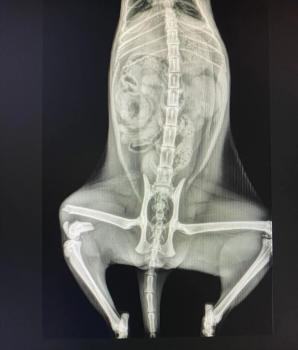

Update 11.04.2026

Bei Dulcinea wurde leider ein Oberschenkelbruch diagnosiert. Die Tierschützer sammeln aktuell Spenden, damit sie bald operiert werden kann.

Sie wurde wahrscheinlich bereits in diesem Zustand ausgesetzt.